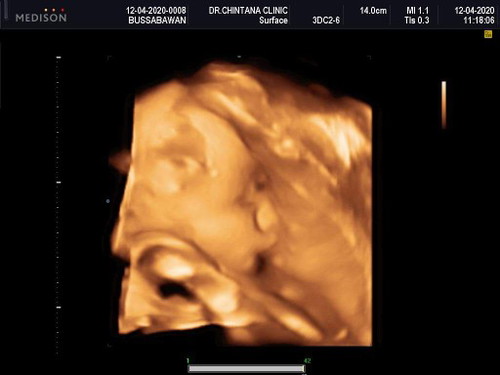

เจ้าหมูของแม่ ถึงจะไม่ได้ร่ำรวยอะไร แต่ดีใจมากที่มีลูก 30+2 แล้ว นับวันรอ??